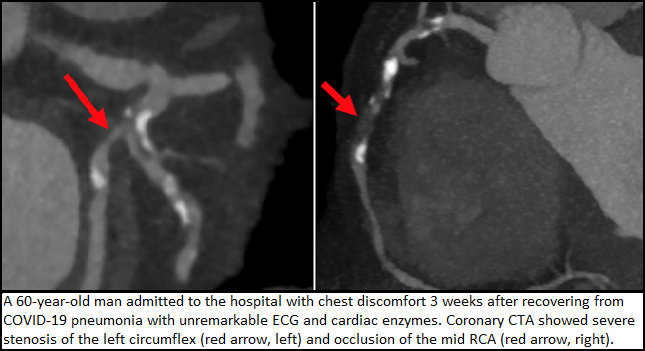

Signs of cardiac damage are seen on CMR even in younger, nonhospitalized COVID-19 patients, according to a study in JAMA Cardiology. Despite the fact that 67% of the patients who volunteered for the study never required hospitalization, 78% had abnormal imaging findings 2 to 3 months after testing positive for the virus, TCTMD Managing Editor Shelley Wood reports. Commentators on Twitter raised some issues with the study.

A multispecialty review commissioned by the Cardiovascular Imaging Leadership Council of the American College of Cardiology summarizes the available evidence and offers guidance for multimodal imaging in the setting of cardiac indications and confirmed or possible SARS-CoV-2 infection. “We felt that it might be helpful for clinicians out in the field to get an integrated expert view bringing in all the opinions, not just one subspecialty, and arriving at some consensus about what we think is most effective in this disease,” senior author Marcelo Di Carli, MD, told TCTMD Managing Editor Shelley Wood.

A recent case report in Circulation suggests nonobstructive chest pain symptoms, presumed to be myocarditis in the setting of COVID-19, may actually be extensive and elusive microthrombi, TCTMD’s Caitlin Cox reports. “This type of injury would not be detectable clinically, as no laboratory test specifically can detect microthrombi,” the researchers say.

A recent case report in Circulation suggests nonobstructive chest pain symptoms, presumed to be myocarditis in the setting of COVID-19, may actually be extensive and elusive microthrombi, TCTMD’s Caitlin Cox reports. “This type of injury would not be detectable clinically, as no laboratory test specifically can detect microthrombi,” the researchers say.

Experts provide guidance around the use of multimodality imaging in the evaluation of cardiovascular complications in patients with COVID-19 in the Journal of the American College of Cardiology. “Routine history, physical examination, laboratory testing, electrocardiography, and plain X-ray imaging may often suffice for such patients but given overlap between COVID-19 and typical cardiovascular diagnoses such as heart failure and acute myocardial infarction, need frequently arises for advanced imaging techniques to assist in differential diagnosis and management,” they say.

The wide-ranging cardiac effects during the acute phase of COVID-19 are now well established, but the potential long-term impact of the disease on the heart remains unclear. TCTMD Managing Editor Shelley Wood spoke with researchers looking into that question. “With this disease,” said John P. Greenwood, MBChB, PhD, “we’ve got no idea of what the sort of short- to medium-term outcomes are going to be and certainly no idea what the long-term outcomes are going to be from a heart perspective.”

The wide-ranging cardiac effects during the acute phase of COVID-19 are now well established, but the potential long-term impact of the disease on the heart remains unclear. TCTMD Managing Editor Shelley Wood spoke with researchers looking into that question. “With this disease,” said John P. Greenwood, MBChB, PhD, “we’ve got no idea of what the sort of short- to medium-term outcomes are going to be and certainly no idea what the long-term outcomes are going to be from a heart perspective.”